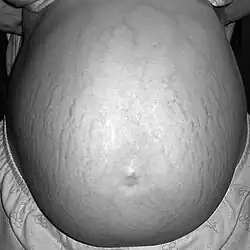

.jpg)

Pregnancy stretch marks, also known as striae gravidarum, are a specific form of scarring of the skin of the abdominal area due to rapid expansion of the uterus as well as sudden weight gain during pregnancy. About 90% of pregnant women are affected.[14]